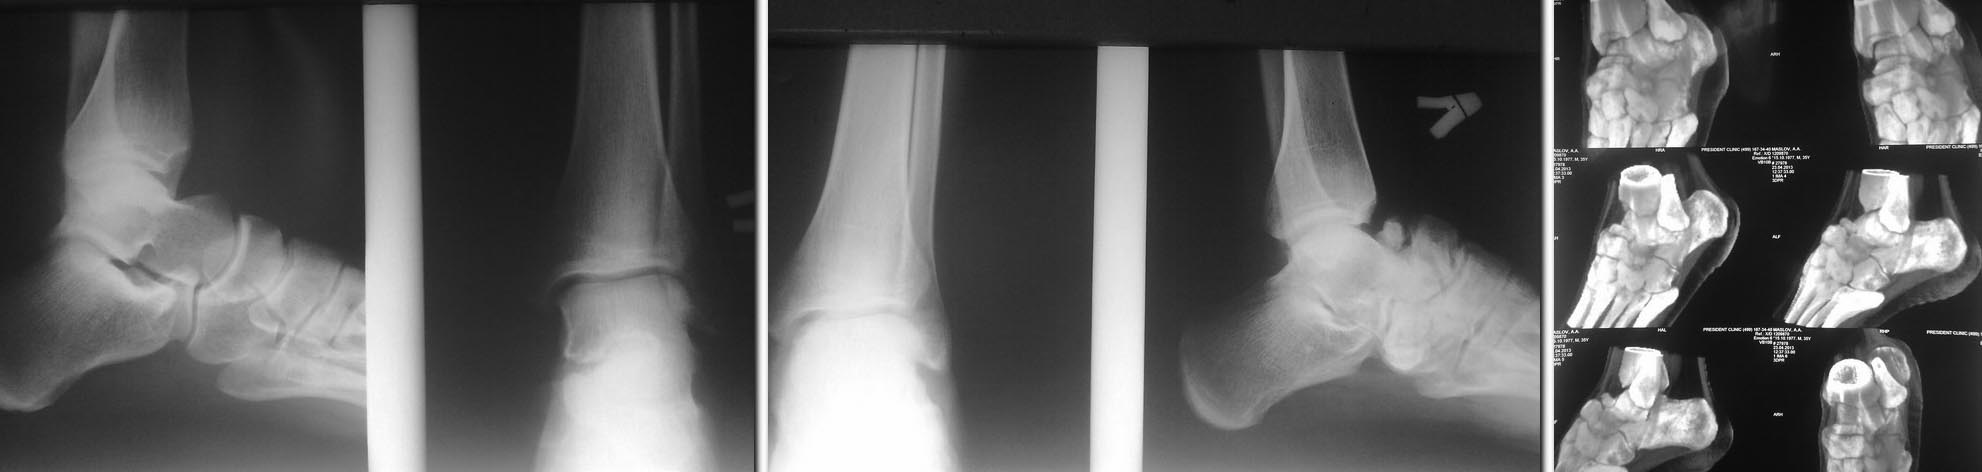

Доброго времени суток, дорогие коллеги. Представляю Вашему вниманию

своего знакомого.

Парень 35 лет получил травму 20 лет назад при падении с высоты. Первая

помощь оказана в одной районной больнице, отболело и забыл... Но 6

месяцев назад пришлось вспомнить; постепенно начали беспокоить боли в

области сустава Шопара после продолжительной нагрузки, периодически

употребляет НПВС (2 раза в неделю). Итак вопрос: кто может помочь

бедолаге? И у кого есть какие идеи решения данного вопроса. Всем спасибо!